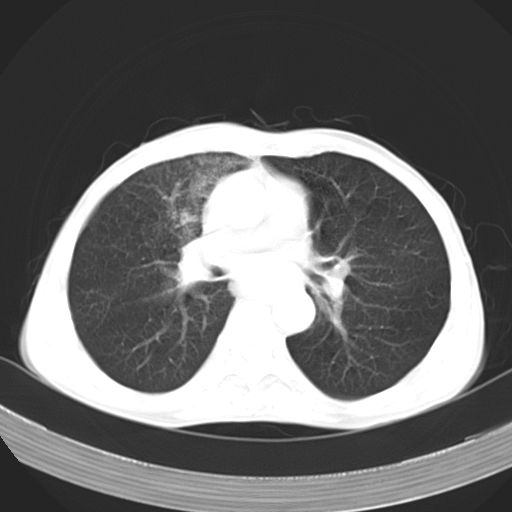

以下是引用苯小孩在2007-5-24 12:47:00的发言:[br]右侧肺门处不均匀密度软组织块影,远端肺组织见斑片模糊影,纵隔内淋巴结明显肿大,边界不清.<纵隔窗第12层面支气管内似见软组织结节>[br]考虑:1、右侧中央性肺癌并阻塞性肺炎并纵隔淋巴结转移可能性大.建议强化或纤支镜进一步检查.[br]2、隆突下淋巴结肿大/食道病变?请做鉴别检查.

以下是引用zhangzhongshou在2007-5-24 12:55:00的发言:[br]1、右肺中叶中心型肺癌并右肺门、隆突下、纵隔淋巴结转移。右肺中叶阻塞性肺炎。

以下是引用jw-830在2007-5-24 15:24:00的发言:[br][br] [br] 考虑右肺中央型肺癌并阻塞性炎症,右肺门及纵隔淋巴结转移。 [br] [br][br]